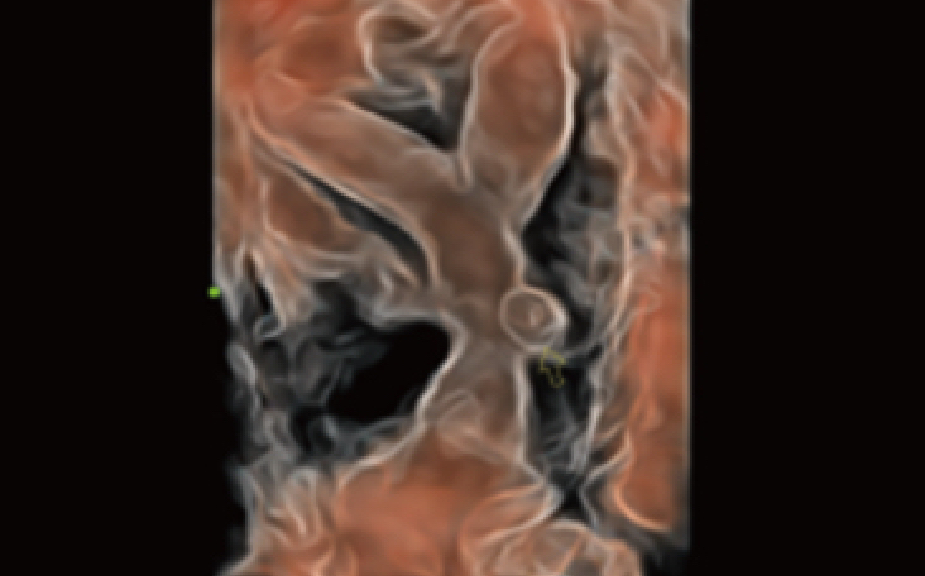

Realizing the increasing importance of ultrasound diagnosis on pelvic ?oor disorders, Smart Pelvic provides a new solution to greatly simplify the operation procedures, and to minimize the exam time for a standardized evaluation on pelvic ?oor. With extremely simple user-interaction, it generates a standard coordinate system and automatically provides all related measurements within a few seconds.